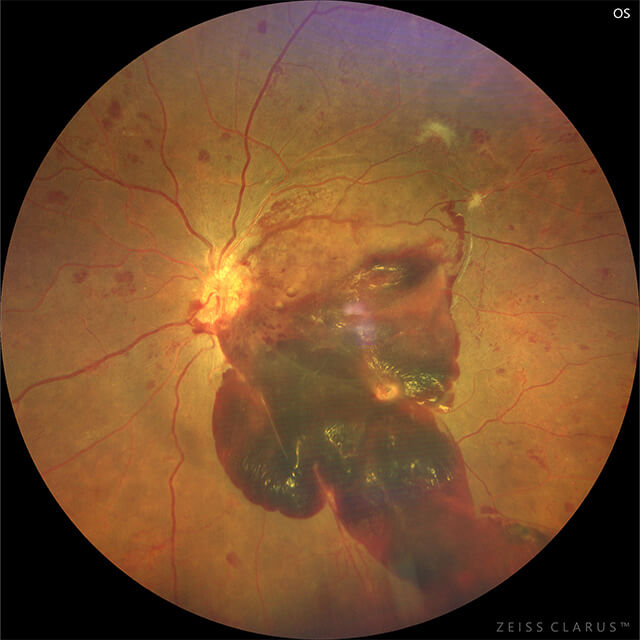

糖尿病の三大合併症の一つであり、日本人の失明原因の第2位を占めています。進行した増殖糖尿病網膜症では、状態によって注射やレーザー治療を行うこともありますが、眼内での出血が広がっていたり、悪い膜の牽引により網膜剥離が生じている場合などは硝子体手術が選択されます。

早期発見と早期治療が大切な疾患です。糖尿病を発症している場合には、これといった眼症状がなくても半年から1年ごとに眼科の受診を心がけてください。